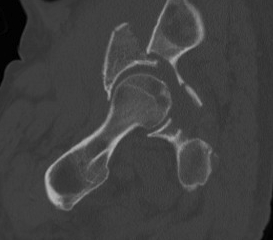

CT

Configuration

1-2 mm sections

CT reconstruction

- remove head to view acetabulum

- beware volume averaging

- used to guide surgery

Diagnose

Loose bodies

Femoral head fractures

Subtle subluxation

Articular steps

Roof arc measurement

5. Transverse

- from greater sciatic notch to AIIS

- obturator foramen not fractured

High - above acetabulum

Low - through acetabulum

Complex / More than one primary fracture line

1. Posterior column & posterior wall

2. Transverse & posterior wall

3. T-shaped

- transverse through acetabulum

- inferior fracture line to obturator foramen

4. Anterior & posterior hemi-transverse

5. Both column

- Y Shaped transverse above acetabulum